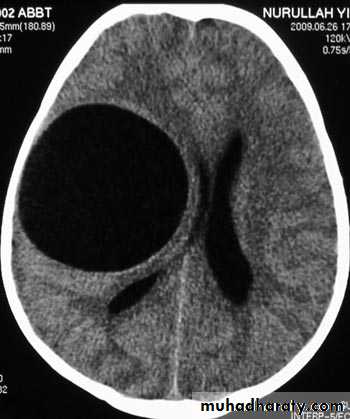

Hydrocephalous

2 typesObstructive ( non – communicating )

Non –obstructive ( communicating )

No obstruction of the ventricular pathway , but the absorption of the csf at the level of arachnoids' granulation is occluded secondary to lodge by blood clot or inflammatory cell or infection post meningitis most commonly to occur post SAH .